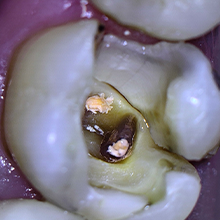

Imagem tomográfica do dente, evidenciando a fratura na mesio-palatina

Exposição da Fratura